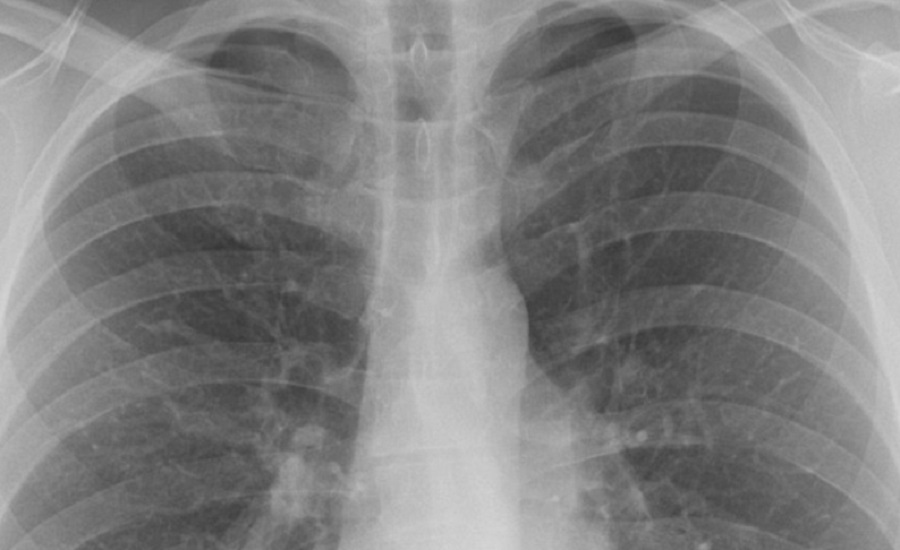

A tüdőrák kezelésének sarokköve a sugárterápia. Ugyanakkor, még ha pontosan alkalmazzák is, a sugárzás károsíthatja az egészséges tüdőszövetet.

A Reports of Practical Oncology and Radiotherapy című folyóiratban megjelent tanulmány a tüdő természetes alegységeire, az úgynevezett lebenyekre összpontosít.

Ahelyett, hogy a tüdőt egyetlen szervként kezelnék, a kutatók felfedezték: az egyes lebenyeknek adott sugárdózis számít. Bizonyos lebenyek, különösen az alsóbbak károsodása növeli a tüdőtoxicitás és a mellékhatások kockázatát.

Hogy megtudják, mennyi sugárzást kapnak az egyes lebenyek, a klinikusok kézzel rajzolják meg az egyes lebenyek körvonalait a CT-felvételeken.

A folyamat betegenként 3-4 órát is igénybe vehet. Ennek eredményeként a lebenyszintű elemzést gyakran kihagyják - annak ellenére, hogy pontosabb előrejelzést adhatna a mellékhatásokról.

A probléma megoldására dr. Vinogradszkij és kollégái egy gépi tanulási modellt képeztek ki, amely automatikusan azonosítja és körvonalazza mind az öt tüdőlebenyt egy vizsgálattal.